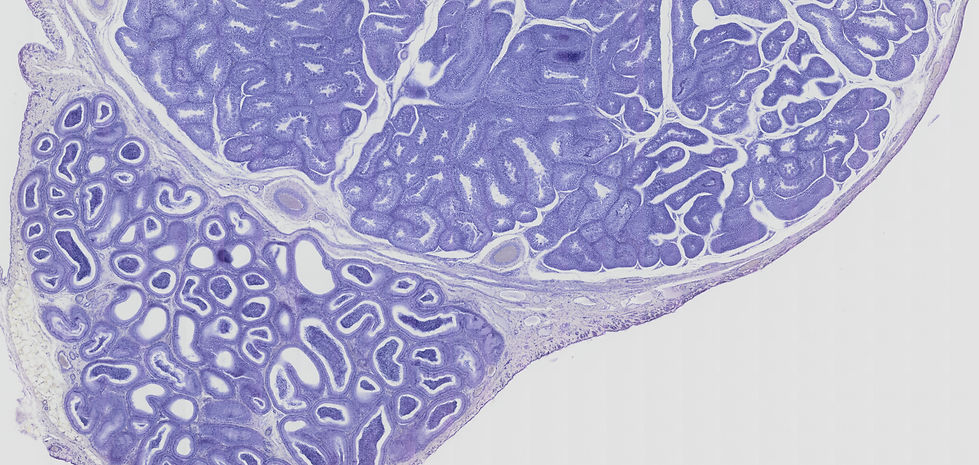

Testiculos

Esta microfotografía muestra un corte histológico del testículo, la gónada masculina responsable de la producción de espermatozoides y hormonas sexuales masculinas. La tinción utilizada es probablemente Hematoxilina y Eosina (H&E), aunque en esta imagen predomina un tono azul/morado, lo que resalta los núcleos celulares.

Análisis de las Estructuras:

Túbulos seminíferos: La mayor parte del parénquima testicular está compuesto por numerosos conductos enrollados, los túbulos seminíferos. Estos túbulos son el sitio donde se lleva a cabo la espermatogénesis, el proceso de formación de los espermatozoides. En un corte transversal, aparecen como estructuras circulares u ovaladas.

Células espermatogénicas: Dentro de la pared de los túbulos seminíferos, se observan varias capas de células espermatogénicas en diferentes etapas de maduración. Estas células se encuentran en un proceso continuo de división y diferenciación, desde las espermatogonias (células madre) en la periferia del túbulo hacia la luz, pasando por espermatocitos primarios y secundarios, hasta las espermátidas y finalmente los espermatozoides maduros (que se observan con sus cabezas orientadas hacia la luz del túbulo).

Células de Sertoli: Dispersas entre las células espermatogénicas, se encuentran las células de Sertoli (también llamadas células de sostén). Son células columnares con núcleos grandes y ovalados, a menudo con un nucléolo prominente. Las células de Sertoli desempeñan funciones cruciales en la espermatogénesis, incluyendo el soporte estructural y nutricional de las células espermatogénicas, la formación de la barrera hematotesticular, la secreción de líquido tubular y proteínas, y la fagocitosis del citoplasma residual durante la espermiogénesis.

Células de Leydig (o células intersticiales): En el tejido conectivo que rodea los túbulos seminíferos, en los espacios intersticiales, se encuentran las células de Leydig (también llamadas células intersticiales). Estas células son de forma poliédrica y tienen núcleos redondos y citoplasma eosinófilo (rosado). Su función principal es la producción y secreción de testosterona, la principal hormona sexual masculina.

Túnica albugínea: Rodeando el parénquima testicular, se observa una capa gruesa de tejido conectivo denso, la túnica albugínea. Esta cápsula fibrosa proporciona soporte estructural al testículo. En la imagen, se señala la túnica albugínea tanto en la periferia como en una invaginación hacia el interior del testículo.

Mediastino testicular: Es un engrosamiento de la túnica albugínea en la parte posterior del testículo, del cual irradian septos de tejido conectivo hacia el interior, dividiendo el testículo en lobulillos. En la imagen, se observa una porción del mediastino testicular, que contiene vasos sanguíneos y linfáticos, así como los conductos de la rete testis.

Organización Funcional:

La microestructura del testículo refleja sus dos funciones principales:

Producción de espermatozoides (espermatogénesis): Ocurre dentro de los túbulos seminíferos, con la participación de las células espermatogénicas y el soporte de las células de Sertoli.

Producción de hormonas sexuales masculinas (andrógenos, principalmente testosterona): Se lleva a cabo por las células de Leydig en el tejido intersticial.